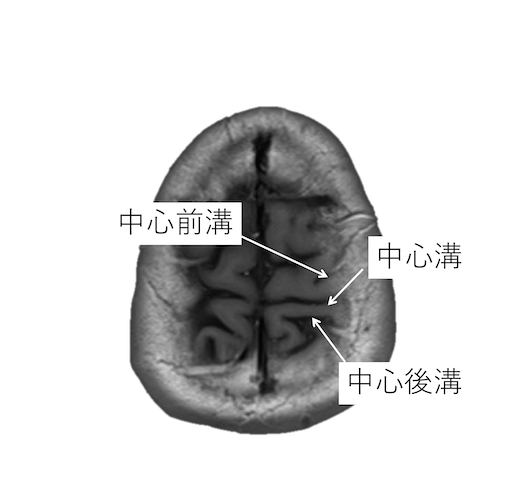

中心溝を同定する際には、以下の4つの原則があります。

・中心前溝は上前頭溝と、中心後溝は頭頂間溝と、連続するが、中心溝が連続する脳溝はない。

・中心後溝の内側端はY字型になり、帯状溝縁部(ちょび髭)は分岐に挟まれる。中心溝の内側端は帯状溝縁部(ちょび髭)のすぐ前にくる。

・脳回の前後幅は中心前回が後回より太い。

・中心前回の手指運動野は後方凸を示す(precentralknob sign)